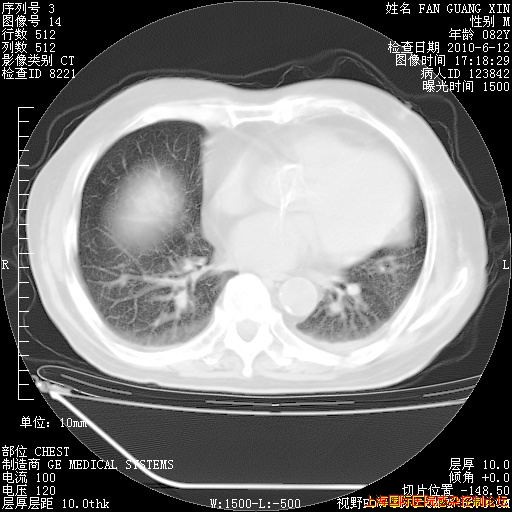

补发6月12日肺部CT肺窗

6月12日肺窗

整整相隔30天的肺部CT好像有所好转啊。甲强龙减量第3天,需要观察体温。

海管,自昨日你和我通完话后,不知您岳父消化道症状有无缓解?体温怎样?阅读7.12日胸部ct,个人认为目前激素治疗是有效的,甲强龙减量是适宜的。因在抗痨治疗,需密切观察肝功、肾功能和血常规。不过,老年、长期住院和大量使用激素,很担心菌群失调发生